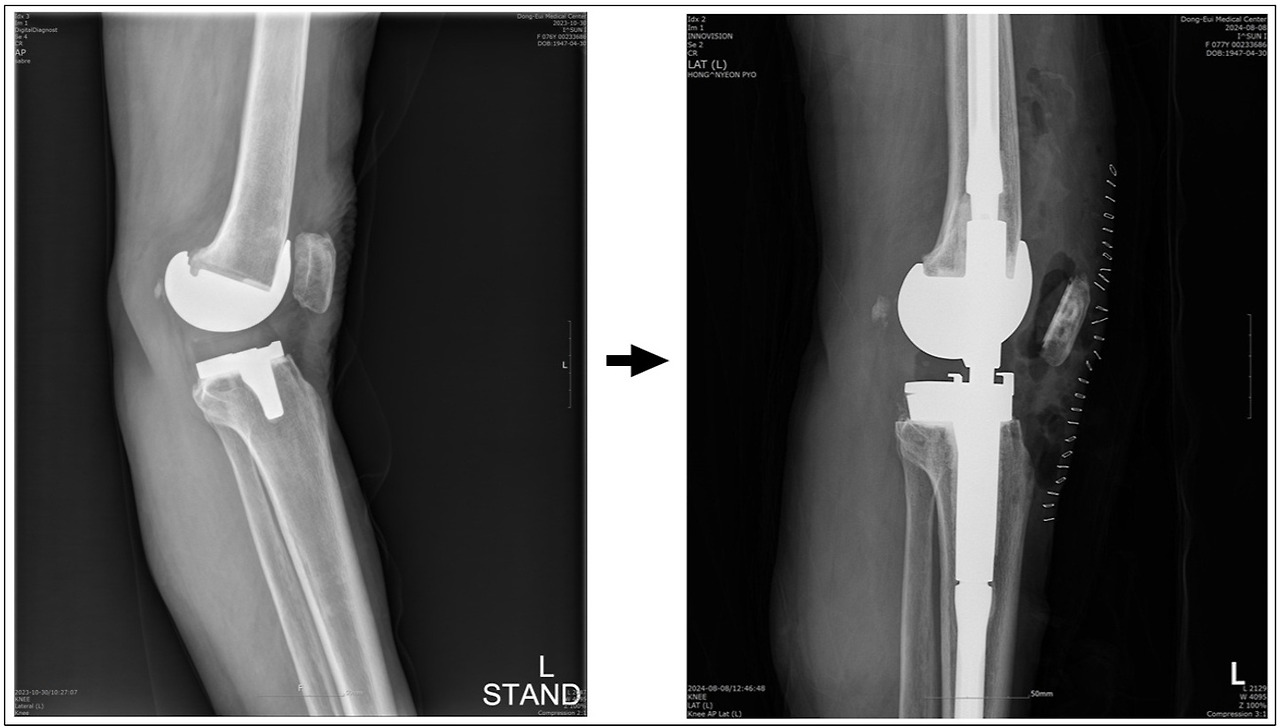

로봇 수술이 기계적으로 뼈를 아무리 정밀하게 절제하더라도, 의사의 판단에 좌우되는 연부조직 균형 조절이 잘 되지 않으면 수술 결과도 좋지 않고, 실제로 그로 인해 재수술하는 경우가 종종 발생한다. 무릎 주위 인대의 긴장도는 수술에 매우 중요한 요소인데, 이것은 사람 손가락 감각으로 판단되는 매우 섬세한 부분이라 로봇 기계로는 할 수가 없다. 따라서 일반적인 기대와는 달리 로봇 수술 후 불만족해 하시는 분들이 꽤 많다. (*아래 사진 설명 -> 좌측 사진은 타 병원에서 로봇 수술 후 무릎이 뒤쪽으로 젖혀져(과신전, Genu recurvatum, back knee) 보행이 어려운 77세 여성 환자의 좌측 무릎 측면 사진. 우측 사진은 본원에서 재수술 후 정상 보행 가능해짐.)

반면, 수술 시간이 길어짐에 따라 세균감염 위험이 높아지고, 로봇 수술에만 나타나는 합병증(e.g. 핀 홀 골절 -> 아래사진)도 생길 수 있기에 [20,21], 비싼 비용을 지불하고 거는 기대와는 달리 환자가 얻을 수 있는 실제적인 장점은 미미하다.

핀 홀 골절 : AG Yun et al. Arthroplasty 2021